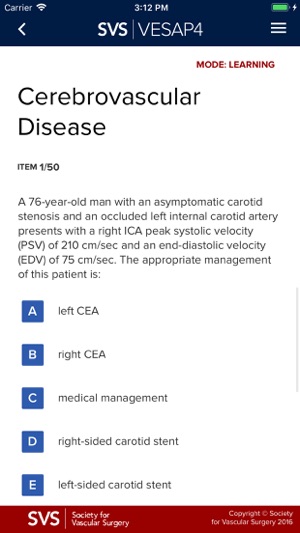

VESAP4 has over 500 questions and includes detailed discussions and references for each question. You may use this product in Learning Mode as often as you like. You will not earn CME credit or MOC self-assessment credit in Learning Mode; however, you will be able to review a rationale for the responses and will access available abstracts in PubMed.

In Learning Mode, you can view the correct answer to each question, the rationale and references. At the end of each session, you may save your answers and return at a later time or you may elect to end the session and view your score. You may use this product in Learning Mode as often as you like and you make take all or part of the exam.